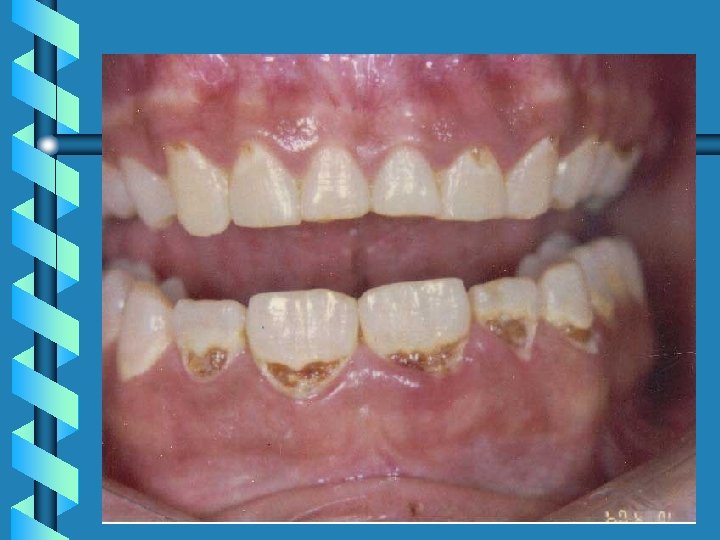

Forensic Odontology • Postmortem dental examination should include examination of: – Missing, unerupted or extracted teeth – Restorations and prosthesis – Decay and broken teeth – Malposition, overlapping, crowding and spacing

• Identifying factors such as cavities, tooth pattern, and general dental health neglect

Forensic Odontology • • Peculiar shapes of teeth Root canal on x-ray Bone pattern on x-ray Bite patterns